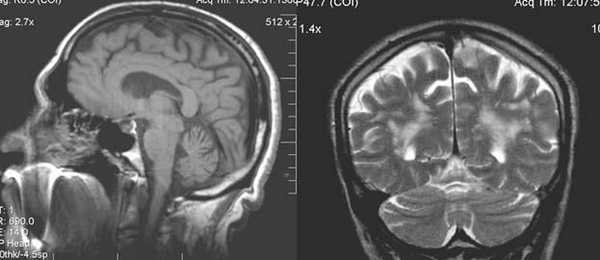

Одним из наиболее информативных среди современных методов нейровизуализации является метод МРТ диагностики.

Только благодаря современным программам, используемым в МРТ диагностике, стало возможным распознавание признаков нарушения мозгового кровообращения уже в первые 24 часа.

Одно из преимуществ МРТ в оценке последствий инсульта - возможность визуализировать нисходящую Валлеровскую дегенерацию аксонов в стволе мозга и кортико-спинальном тракте на стороне поражения.